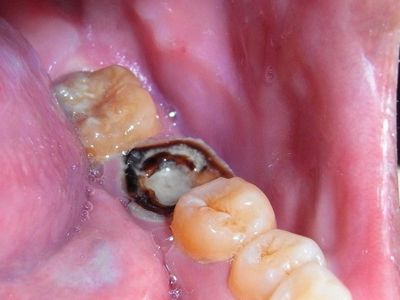

3、患有龋齿。有几种情况需要重视,比如虫牙,需要尽快处理,才能防止继续出现。

4、治疗期间,还需要加强补牙。另一种情况,需要由外科医师评估后决定是否继续补牙。如果医生认为患有龋齿,则需要继续治疗。